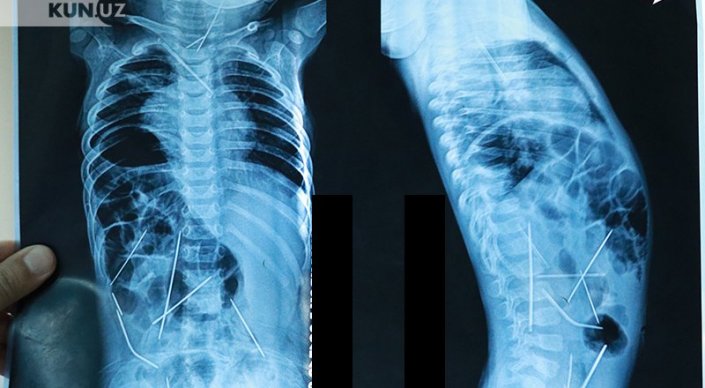

Ташкентские врачи показали годовалого мальчика, в теле которого было найдено 16 швейных иголок, сообщают "Новости Узбекистана". По их словам, сейчас его состояние оценивается как стабильное.

Напомним, маленький Азизбек Абдумаджидов поступил в Республиканский научный центр экстренной медпомощи в середине января с 16 иглами в теле. 13 иголок были удалены в ходе девятичасовой операции, три - до сих пор остаются, но, по уверению медиков, угрозы для жизни малыша не представляют, и их можно извлечь позже.